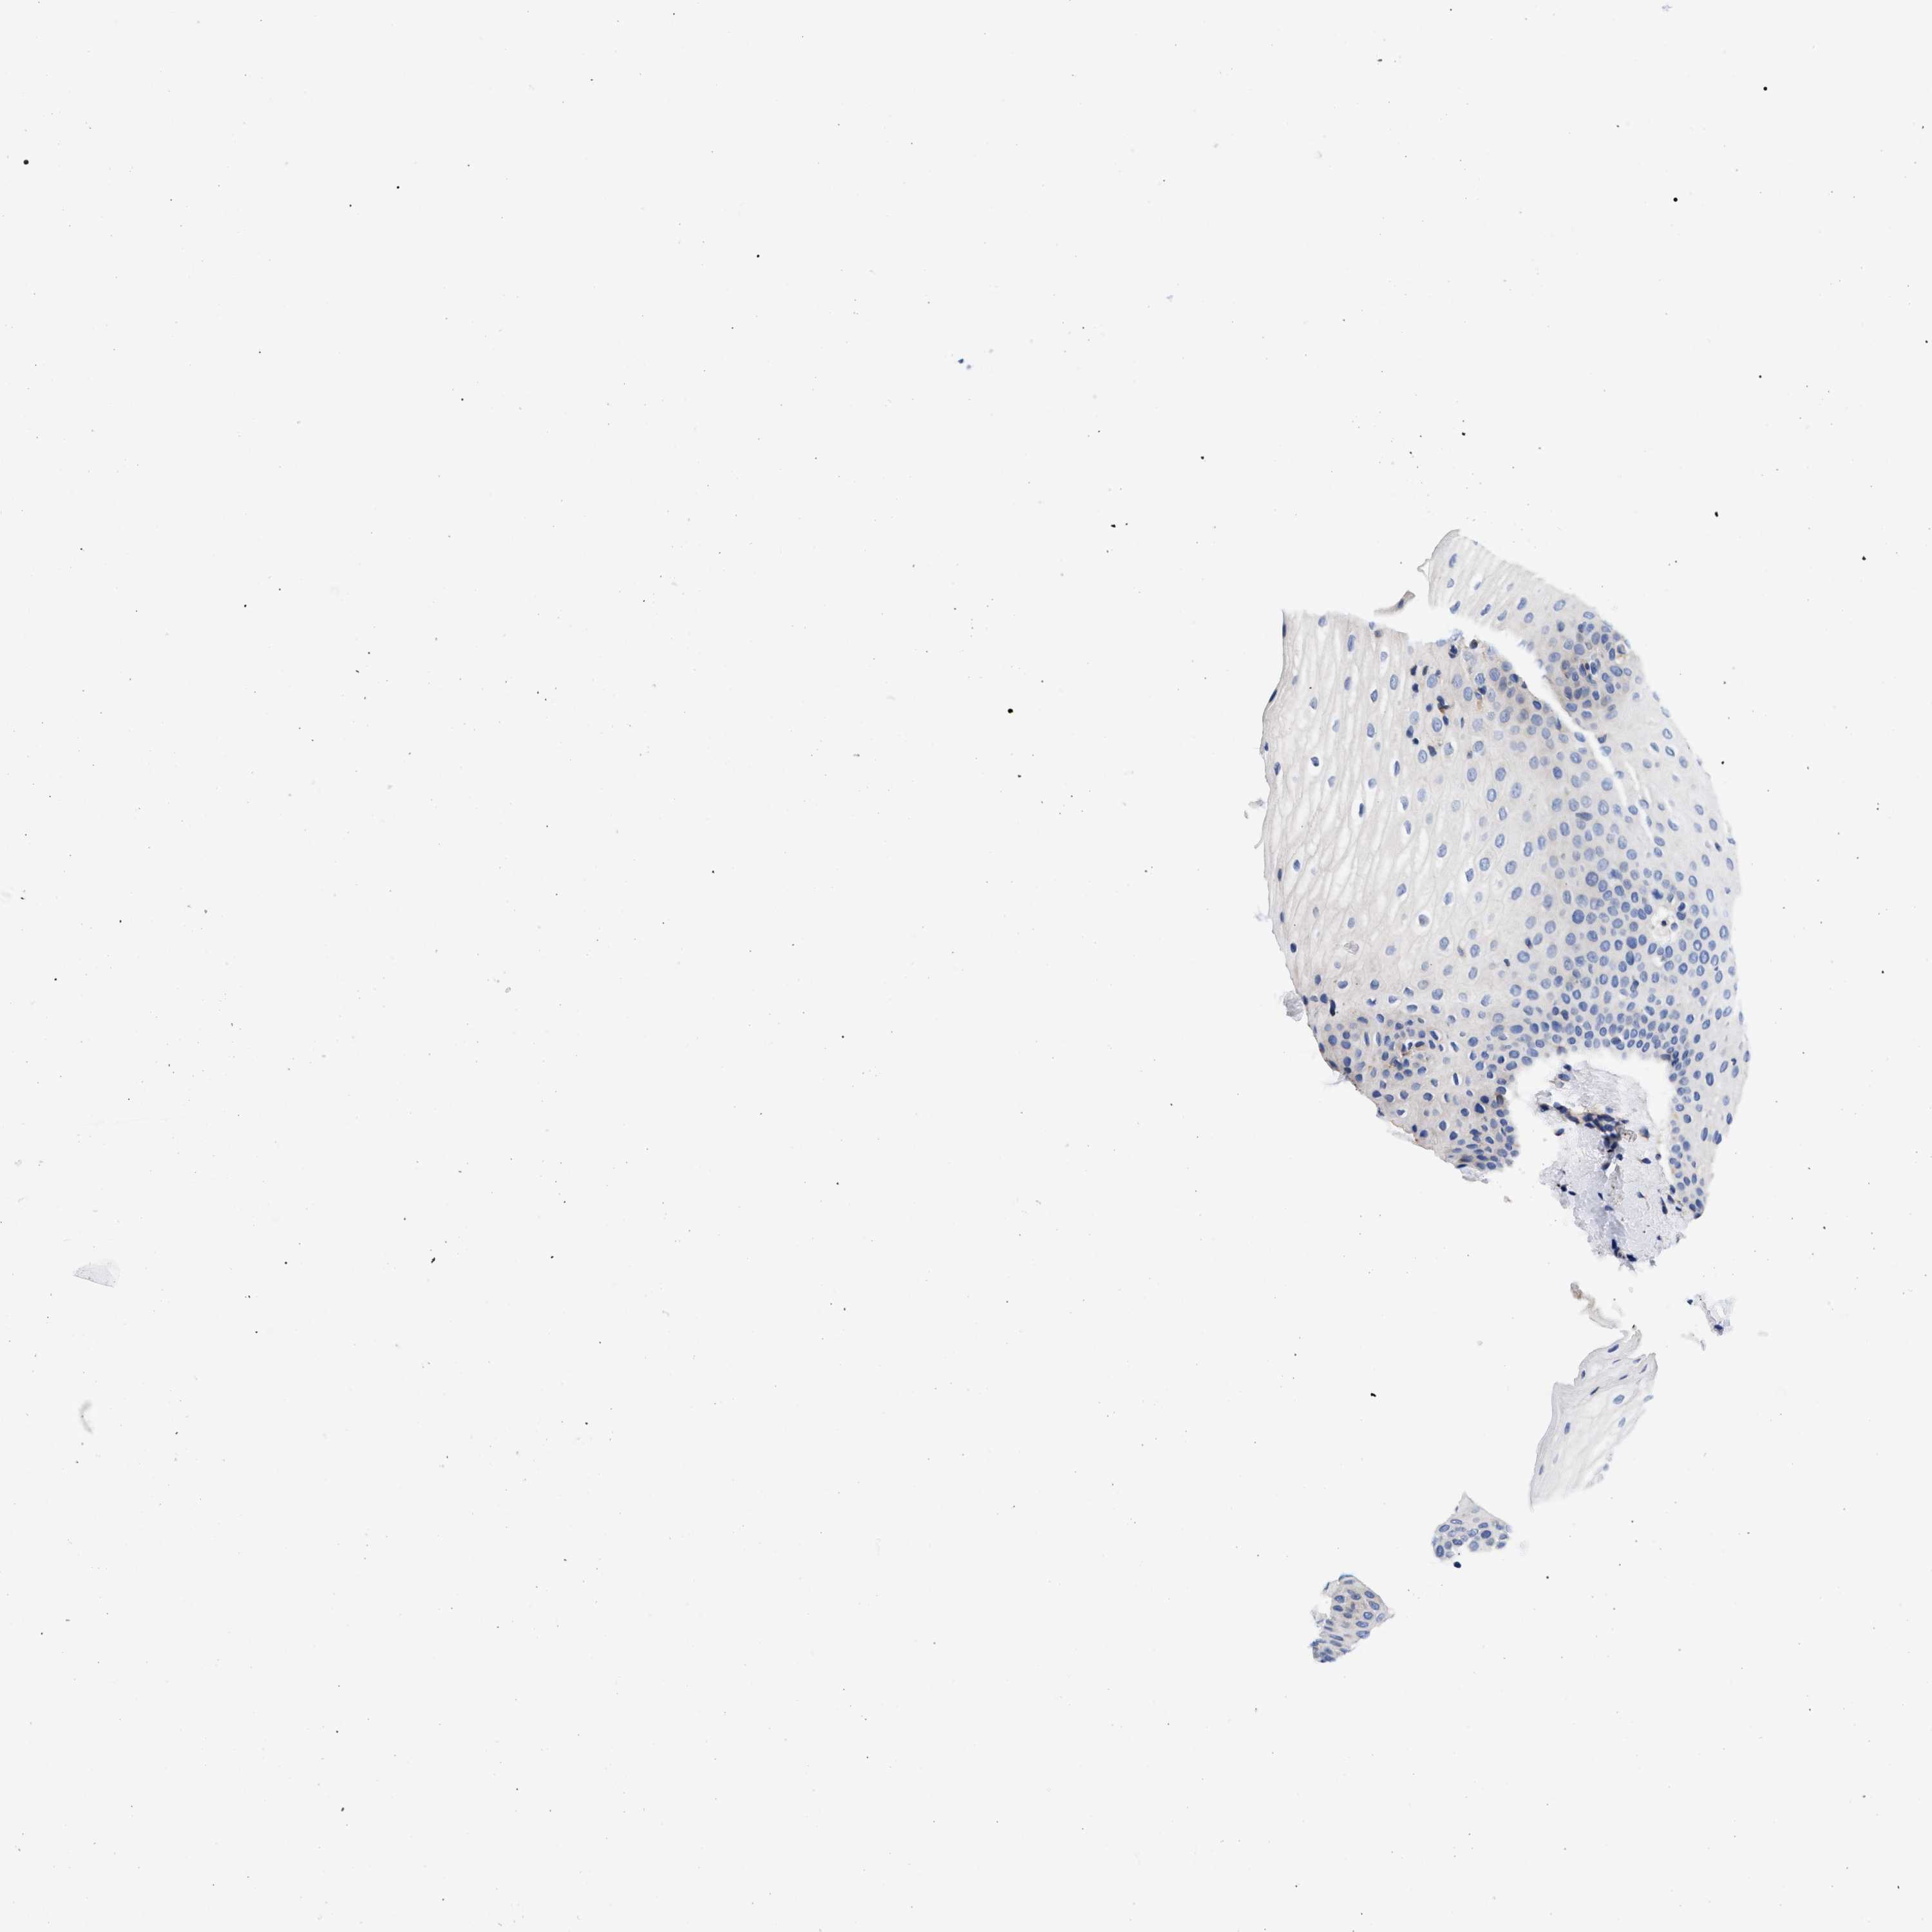

TISSUE PRIMARY DATA ORAL MUCOSA Show tissue menu

ORAL MUCOSA - Antibody stainingi

Antibody staining in the annotated cell types in the current human tissue is reported as not detected, low, medium, or high, based on conventional immunohistochemistry profiling in selected tissues. This score is based on the combination of the staining intensity and fraction of stained cells.

Each image is clickable and will lead to virtual microscopy that enables deeper exploration of all samples and also displays staining intensity scores, fraction scores and subcellular localization as well as patient and tissue information for each sample.

Antibody HPA021165Antibody HPA021753Antibody HPA021760

Squamous epithelial cells Not detectedLowNot detected